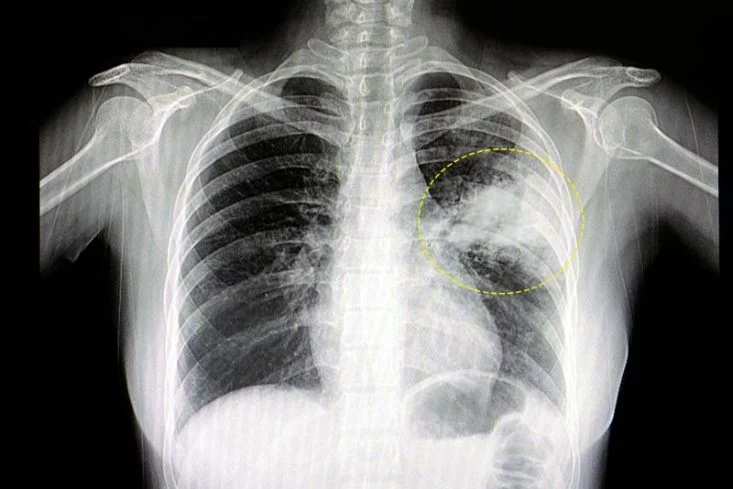

La neumonía es un tipo de infección respiratoria aguda que afecta a los pulmones. Éstos están formados por pequeños sacos, llamados alvéolos, que —en las personas sanas— se llenan de aire al respirar. Los alvéolos de los enfermos de neumonía están llenos de secreciones purulentas y líquido, lo que puede dificultar la respiración y limitar la oxigenación de la sangre en los pulmones. Esta enfermedad puede ser causada por virus, bacterias, hongos o parásitos.

Los síntomas de neumonía pueden ser generales, como fiebre, escalofríos, malestar general, o más específicos, como tos con secreción mucosa o purulenta, dolor en el pecho o falta de aire. Y muchas veces los pacientes llegan al diagnóstico cuando ya se encuentran en instancia de internación, por eso la prevención es clave para evitar casos de gravedad.